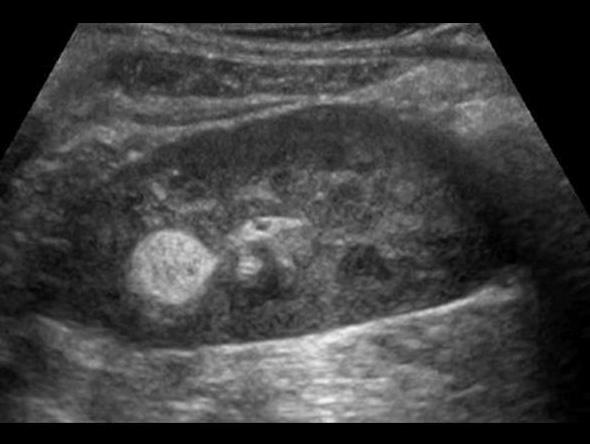

right kidney

Angiomyolipoma

benign fatter renal tumor

80% involve right kidney

echogenicity is gretr than of equal to the renal sinus

right kidney

Angiomyolipoma

benign fatter renal tumor

80% involve right kidney

echogenicity is gretr than of equal to the renal sinus